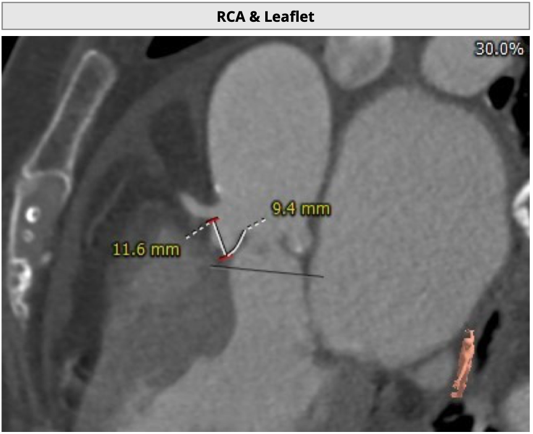

主动脉根部评估

CT 数据显示该患者为三叶式主动脉瓣

TaurusNXT植入过程

考虑患者左冠开口偏低,左瓣叶冗余影响左冠血流,预置GuidezillaII支撑保护,之后采用TaurusAtlas 22mm球囊预扩张,植入AV26 TaurusNXT主动脉瓣,起搏140次/分频率下,在左右重合位瓣膜释放达到工作位,造影显示锚定位置理想,之后在右窦中心位下再次确认植入位置,同时超声评价瓣膜位置及血流动力学情况,最终0位精准释放瓣膜。无回收,无球囊后扩张,未植入冠脉支架。术后即刻超声心动图评估显示瓣膜位置良好,微量瓣周漏,主动脉瓣口峰值流速为1.80m/s,平均跨瓣压差为5mmHg,有效瓣口面积 2.4cm2,血流动力学指标理想。在线专家称赞陈绍良教授、张俊杰教授团队完美完成了一例高冠脉风险、重度主动脉瓣狭窄TAVI手术。